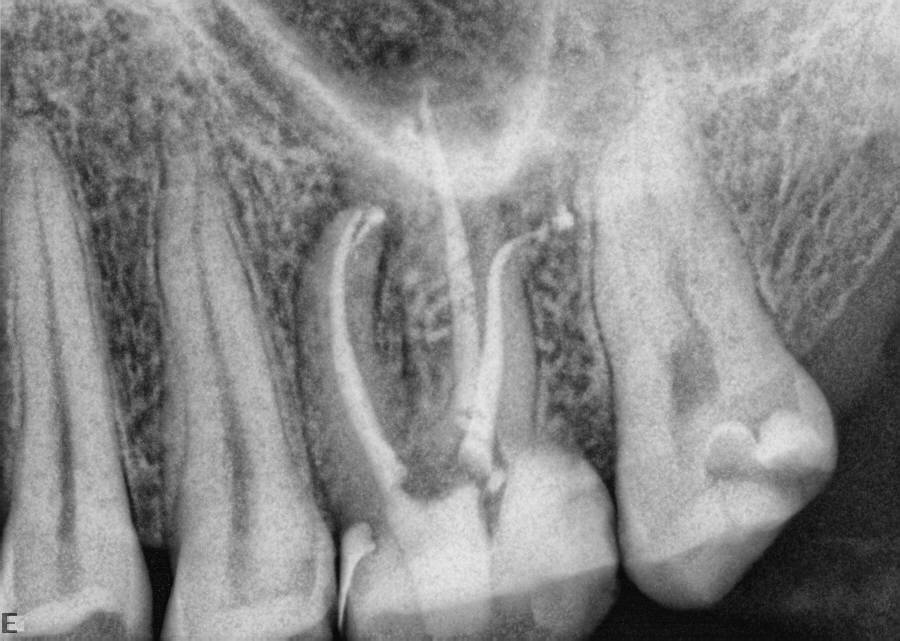

Figure 4 through Figure 10 depict several teeth that have conservative accesses while still allowing the clinician to adequately instrument and clean each tooth to achieve effective root canal therapy. The success of these cases still hinges on the proper cleaning and shaping of the root canal system, and while conservative accesses are desirable, too small of an access can lead to missed canals, poor instrumentation, improper cleaning, and, ultimately, a failed procedure.

Fig 7. Conservative access does not prevent the “popping” of six or seven lateral canals on this particular molar.

Figure 7